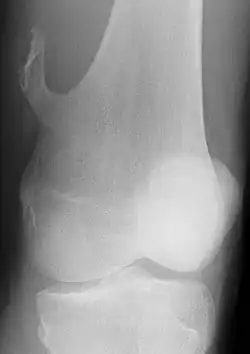

Die Begriffe Osteochondrom, Ekchondrom und kartilaginäre Exostose beschreiben gutartige Knochentumoren. Solange der Tumor nicht verknöchert ist, spricht man vom Ekchondrom oder kartilaginärer Exostose. Als Osteochondrom wird der Tumor nach Verknöcherung bezeichnet. Diese Tumoren wachsen gestielt vom gelenknahen Knochen (Metaphyse) aus. Es sind die häufigsten gutartigen Knochentumoren. Sie machen sich meistens durch Wachstum im Kindesalter bemerkbar. Nach Abschluss des Knochenwachstums im Erwachsenenalter wachsen die Tumoren meist nicht weiter.